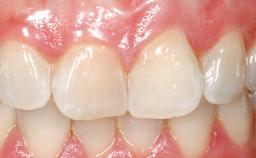

A 33-year-old female patient presented with an upper left central incisor that required extraction after a failed endodontic therapy. The tooth had been traumatized when the patient was a teenager and had undergone several endodontic treatments, including two apicectomy procedures. The patient was in good health and did not smoke. Clinical examination showed that the patient had a high lip line. In full smile, the gingival margins of the upper teeth were visible to the first molars. The gingival margins of central incisors 11 and 21 were only just showing. Examination of tooth 21 confirmed that the tooth was mobile and had hypererupted by 1 mm.

Lip Line No exposure of papillae Exposure of papillae Full exposure of mucosa margin

Periodontal Phenotype Low-scalloped, thick Medium-scalloped, medium-thick High-scalloped, thin

Mesio-Distal Space Symmetry +/- 1 mm of contra-lateral tooth